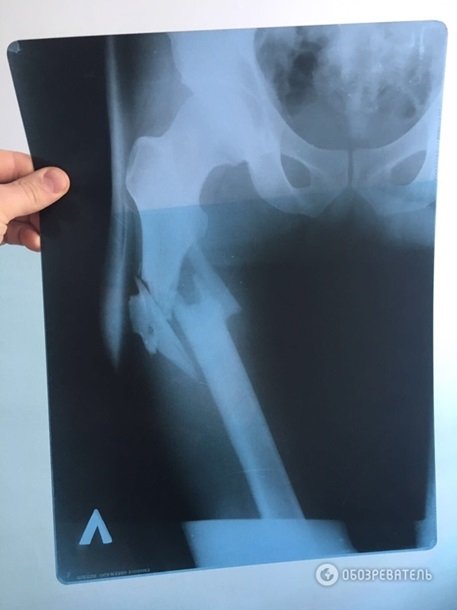

Під час допиту лікар, який оперував постраждалого В'ячеслава Хімікуса, підтвердив, що на місці перелому у пораненого уламки кістки зміщені вниз від таза. Це підтверджує, що Пашинський вистрілив зверху в ногу Хімікусу, а не з положення лежачи, як нардеп стверджував раніше.

Видання також оприлюднило рентгенівський знімок простреленої ноги Хімікуса. Зважаючи на положення вхідного і вихідного отворів від кулі, можна припустити, що куля «йшла» зверху вниз.Тому, як зазначило джерело, у слідства виникають вагомі сумніви в довірі до свідчень Пашинського.